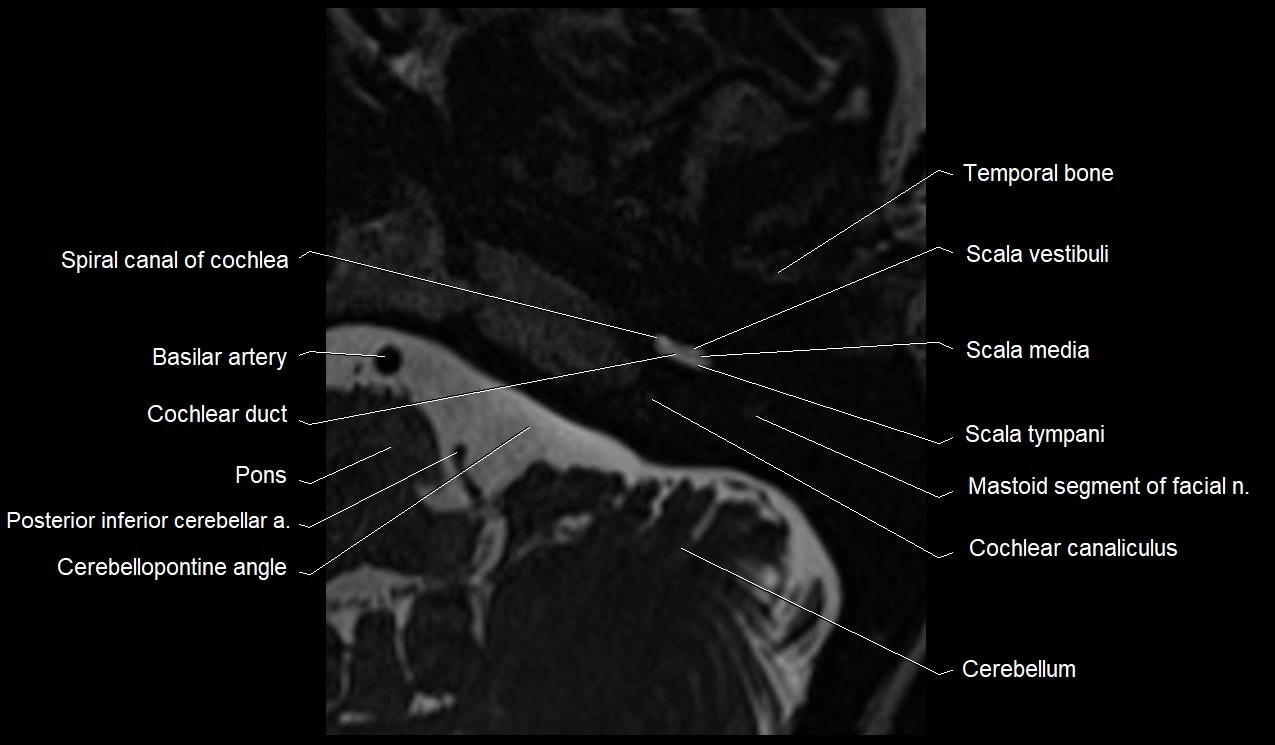

MRI images

image